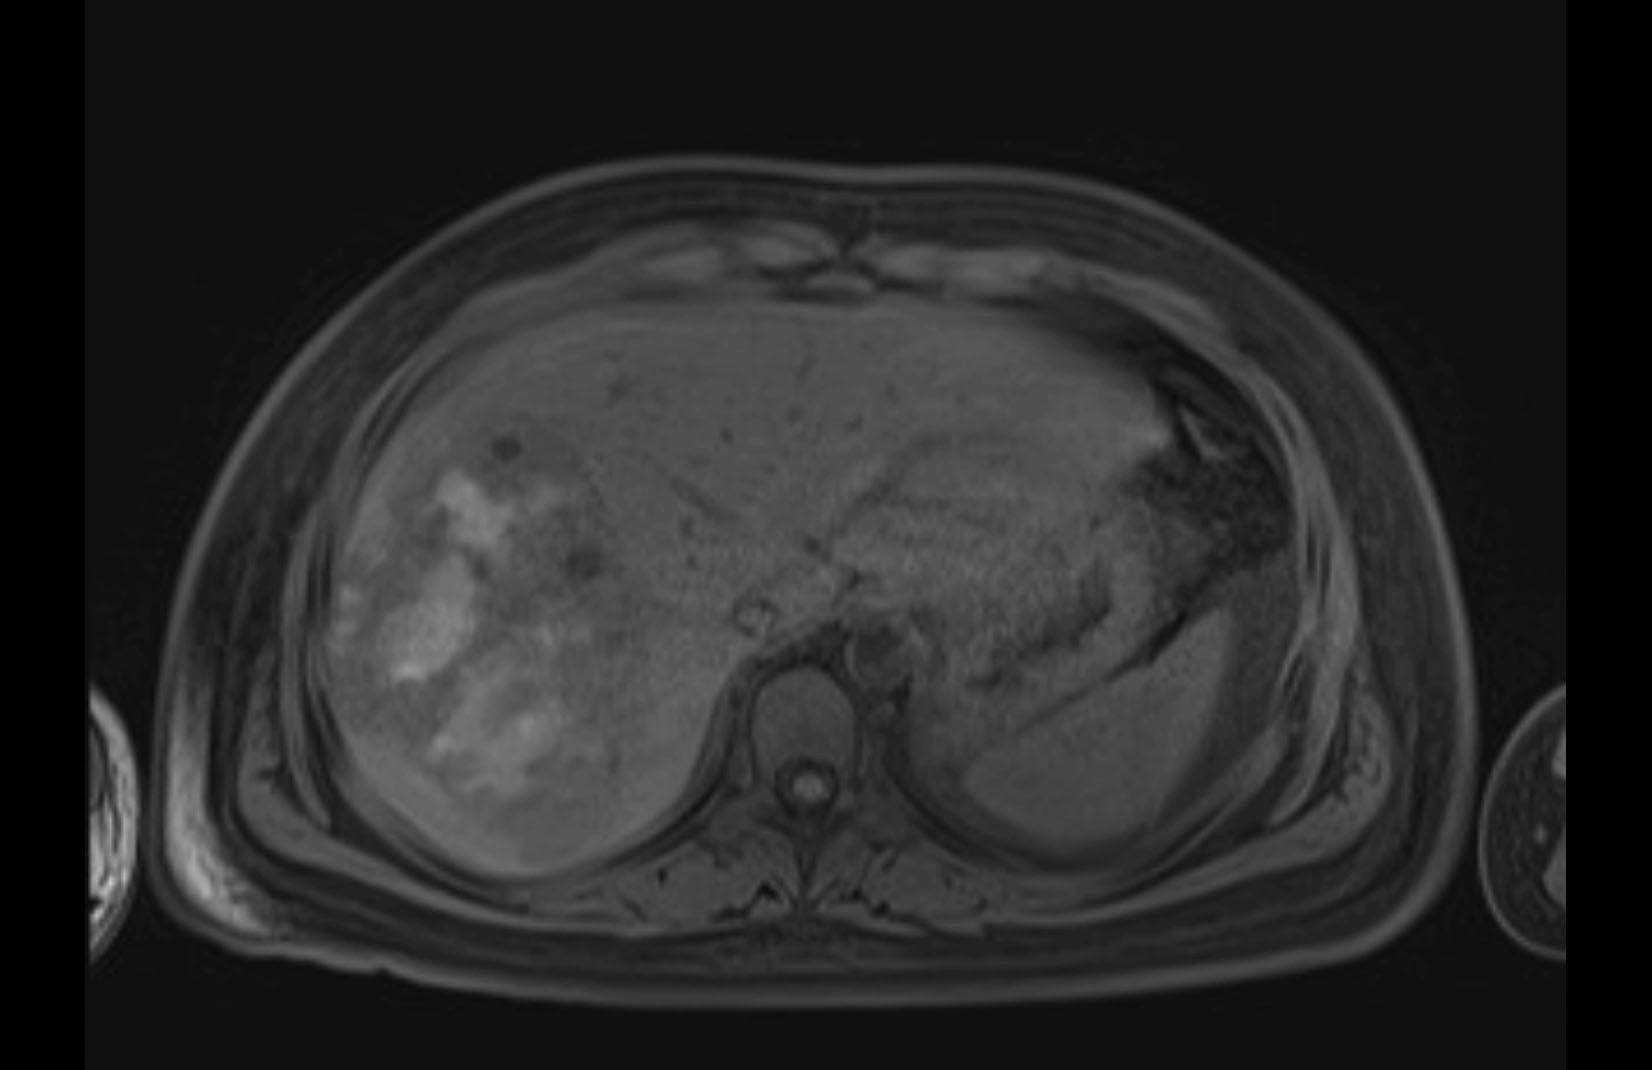

Imaging Analysis

Look through the patient's CT scan to identify any areas of concern for the necessary procedure.

MRI T1

MRI T2

Based on initial findings, which issue(s) would you be most concerned about?